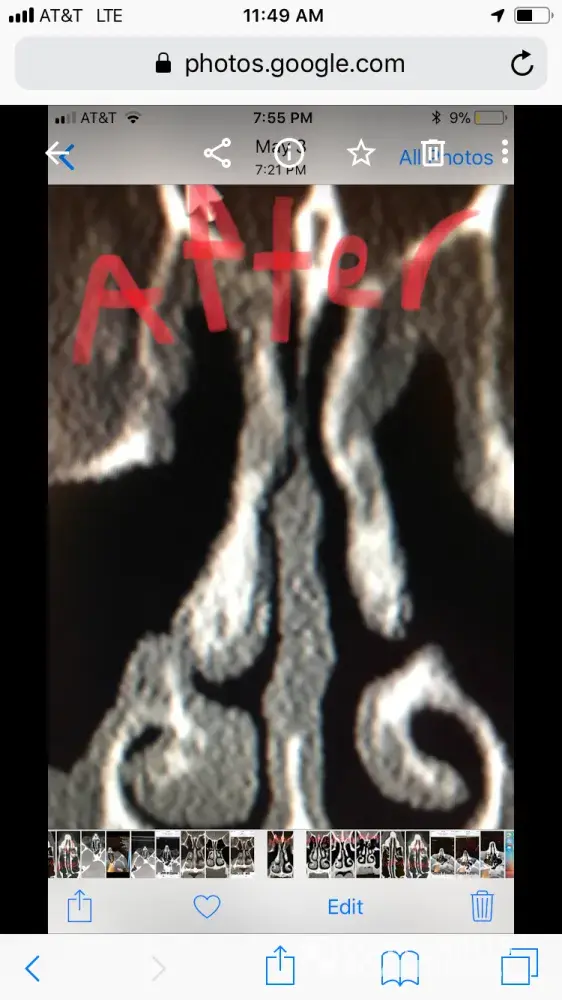

For people reading this, I have included x-ray images of the inside of my nose, before and after my surgery with him. As you can see from these images, my nasal airway was equally open on both sides, before surgery, and the septoplasty didn't need to be done. By performing it, he severely narrowed the right side of my nasal airway.

He performed this unnecessary surgery to collect that additional insurance money. There is no other explanation for this. Furthermore, when I later contacted him, and told him that my breathing was worse, and I suspected it was a problem with my septum, he told me that he wouldn't be able to perform the revision septoplasty (make the septum way it was before). Therefore, not only is he greedy, by performing unnecessary surgeries, but he is incompetent, for not being able to fix his mistakes.

Dr Raviv performed two surgeries on me: endoscopic sinus surgery (where they widen the sinus passages), and septoplasty (where they straighten the septum). The septoplasty, however was completely unnecessary, and severely narrowed the right side of my nasal airway. For people reading this, I have included x-ray images of my sinuses, before and after my surgery with Dr. Raviv. As you can see from the surgery, my airway was much more open, and equal on both sides, before my surgery with him.